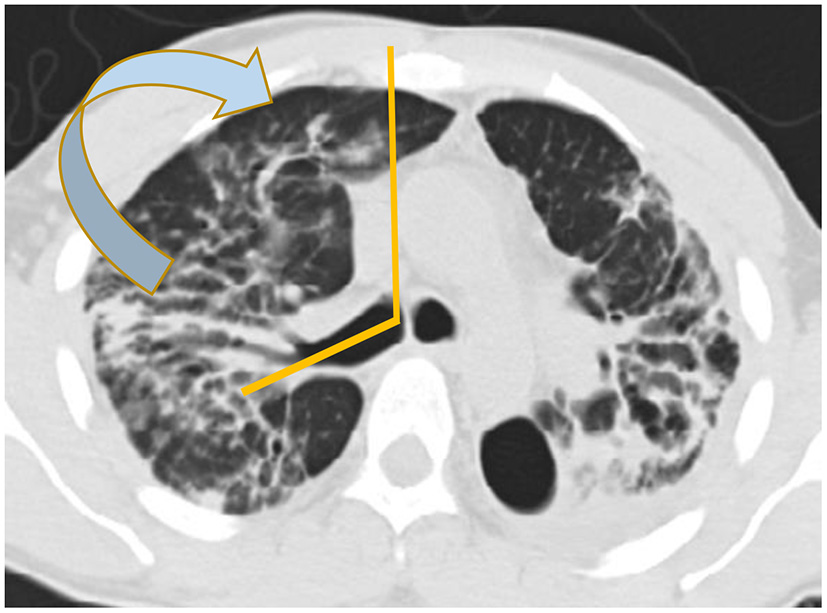

There are basically two main types of sarcoidosis, fibrotic and non-fibrotic (32). The non-fibrotic type of sarcoid has pulmonary nodules and lymphadenopathy (Figure 6). The major feature of the progression of the fibrotic type of disease is volume loss with tenting of the hemi-diaphragms. Fibrotic sarcoid primarily affects the posterior aspect of the upper lobes and as such displaces the right upper lobe bronchus (32). In particular, the radiologist can measure the angle between a line traversing the right upper lobe bronchus and a sagittal line connecting the sternum to the vertebral body. The angle is called the Right Upper Lobe Bronchus Angle (RUL-BA) (Figure 7). The angle increases with the fibrotic phase of the disease and can be used as a biomarker for disease progression (32).

Figure 7

Stage 4 sarcoidosis is associated with progressive loss of volume of the upper lobes with displacement of the right upper lobe bronchus posteriorly as seen in this image.